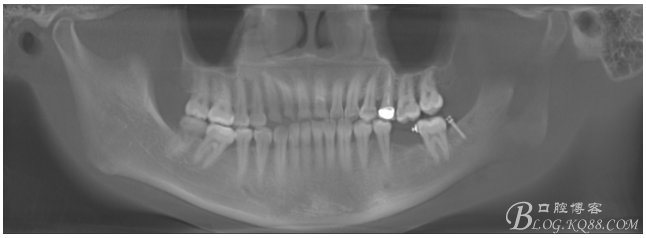

植入5.0X10mm植體

術(shù)后CT片

注:此時并不能拆除37遠中支抗釘,需等待取模型時再拆除支抗釘和舌側(cè)扣,防止37傾斜復(fù)發(fā)。